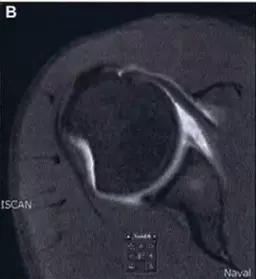

1. Hill-Sachs 损伤和反 Hill-Sachs 损伤

肩关节脱位时,肱骨头和关节盂发生撞击,肱骨头表面凹陷性骨折。

肩关节前脱位时发生的肱骨头后外侧凹陷性骨折,是经典的 Hill-Sachs 损伤(Hill-Sachs lesion);

-

而肩关节后脱位时发生的肱骨头前内侧凹陷性骨折,是反 Hill-Sachs 损伤(Reverse Hill-Sachs lesion/ McLaughlin lesion)。

Hill-Sachs 损伤的 MR 片(来源:Hill-Sachs Injuries of the Shoulder)

MRI 示反 Hill-Sachs 损伤程度 (来源:Anatomical Reconstruction of Reverse Hill-Sachs Lesions Using the Underpinning Technique. Orthopedics May 2012 - Volume 35 · Issue 5: e752-e757)